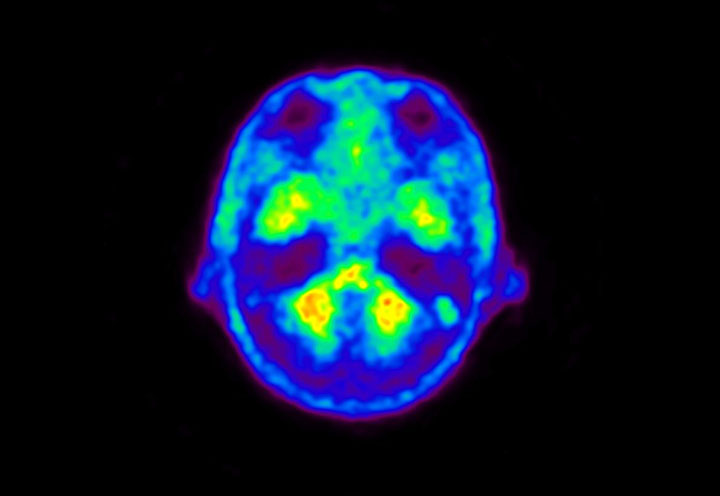

Head / Case5 : Amyloid

Axial

Courtesy : Kindai University Hospital

- Imaging protocol

- Injected dose: 4.27 MBq/kg, 18F-Flutemetamol

- Uptake time: 99 minutes

- Scan time: 20 minutes